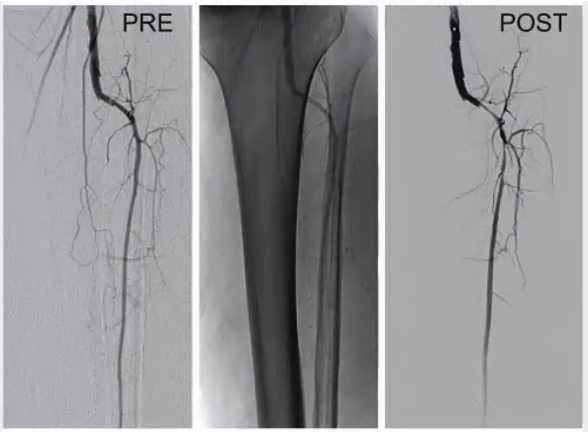

leriche syndrome (aorto-occlusive disease)

leriche syndrome

ideal femoral access location

enter skin inferomedial to the femoral head

femoral head provides a hard surface for hemostasis

at the level of the femoral head, the femoral artery and nerve are side by side